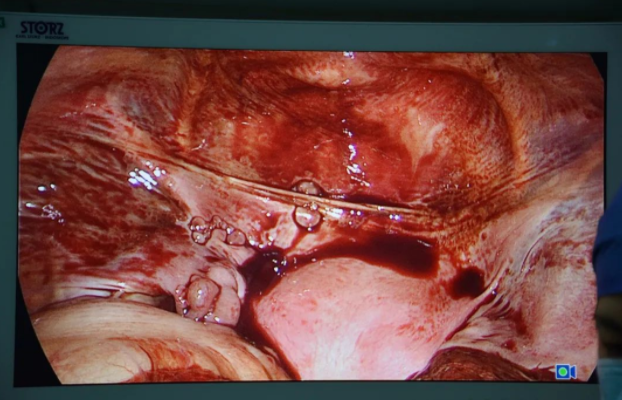

术中见处女膜闭锁、无孔,曾华副院长予10ml注射器针头穿刺,可抽出暗褐色液体,沿注射器针头方向行“X”形切开处女膜,阴道口见一厚约0.8cm肌性纵隔连于阴道前后壁,宫腔镜进入阴道,向上进入左、右宫腔,纵隔延续至宫底部,顶端可见左右两侧输卵管开口及宫角,内膜光滑平整。腹腔镜下盆腹腔可见大量巧克力样物,子宫横径增宽,色红润,表面平,双侧输卵管、双卵巢外观未见明显异常。予冲洗盆腹腔,清理干净巧克力样物,术后患者腹痛消失,经过一段时间的住院恢复,小周开开心心的重返校园。